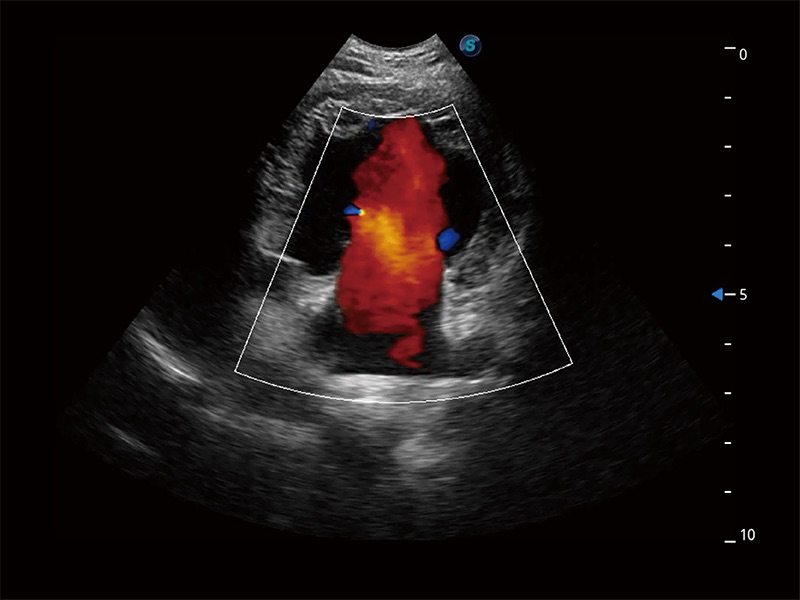

在傳統(tǒng)二維血流成像的基礎上,呈現(xiàn)血流的立體感,具有動感的生命力之美。即便是微小的血管也能輕松應對,提高了血流的視覺敏感性。